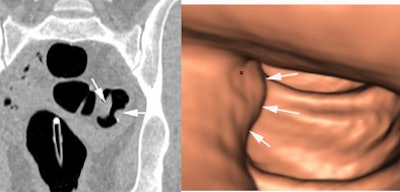

![]() |

| CAD detected the same types of false positives as the unassisted readers. All images and data courtesy of Dr. Stuart Taylor. |

| CAD can help: Before CAD, two readers incorrectly reported a bulbous fold as cancer, while only one reader called it a positive finding post-CAD. |